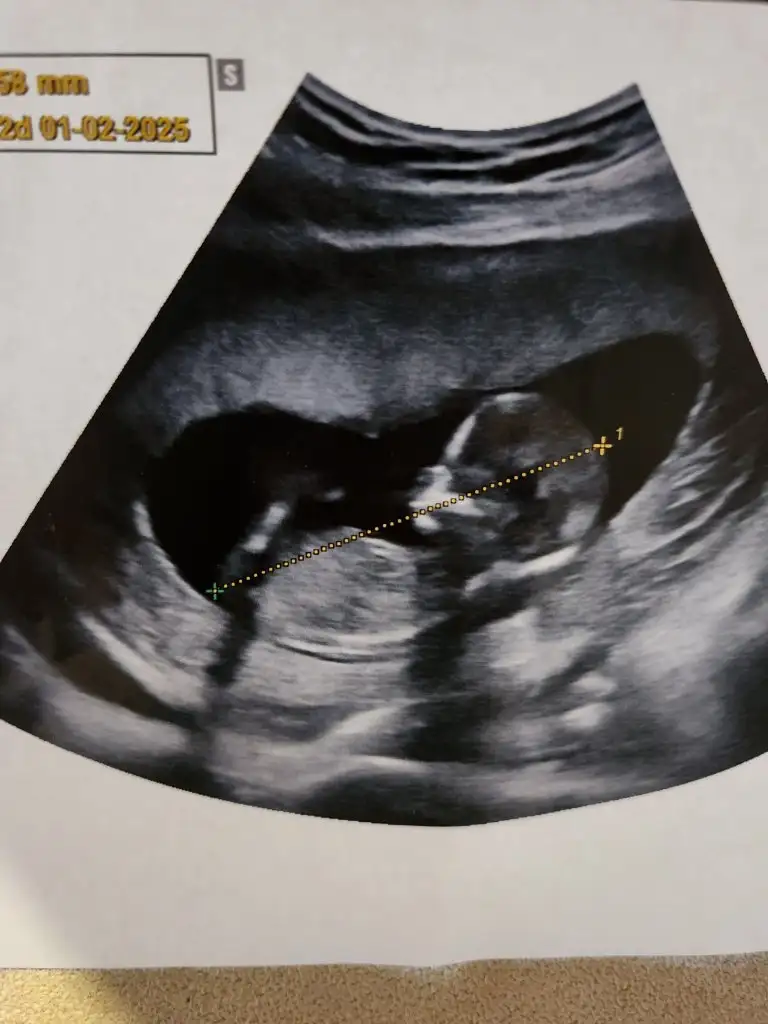

Ya bana dr %99 erkek bu dedi ama simdilik kimseye soylemeyelim lutfen dedi fetal dna istedi onun sonucuna bakcak da. E ben herkese soyledim erkek diye😂 %99 erkek diyip de degisir mi sizce ya? 🤭 bu da bebemin fotosu pipi en altta sanki gorunuo🤔

Eklentiler

• 1000035016.webp

1000035016.webp

30,8 KB · Görüntüleme: 128